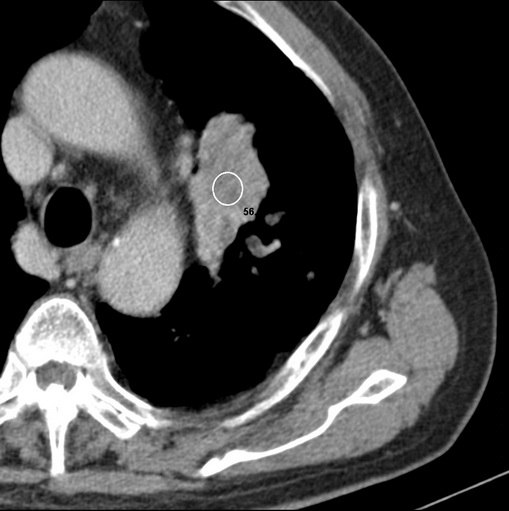

男性患者 81岁 咳嗽 咳痰 咯血

有强化 考虑肺癌肺门淋巴结转移

左肺中心型肺癌并:1.左肺阻塞性肺炎;2.纵隔淋巴结肿大;

强化较典型,左上肺癌并纵膈淋巴结转移;左上肺结核并空洞形成;胸膜增厚.

考虑左上肺癌并阻塞性肺炎,左肺转移、左肺门及纵隔淋巴结转移。

支持左侧中央型肺癌伴肺门及纵膈淋巴结转移。

标题: 考虑左侧中央型肺癌可能性大

肿块贴近左肺门,包绕左上肺动脉,形态不规则。肿块增强扫描中度强化。纵膈内主动脉弓左旁间隙、气管隆突前、下间隙见多枚淋巴结影。综上考虑左侧中央型肺癌可能性大。图片没有完整上传,尤其是左肺上叶支气管分支层面没有上传,因此不好判断是叶支气管中断还是段支气管中断。另外,下图红色部分所示是“黏液支气管征”吗?